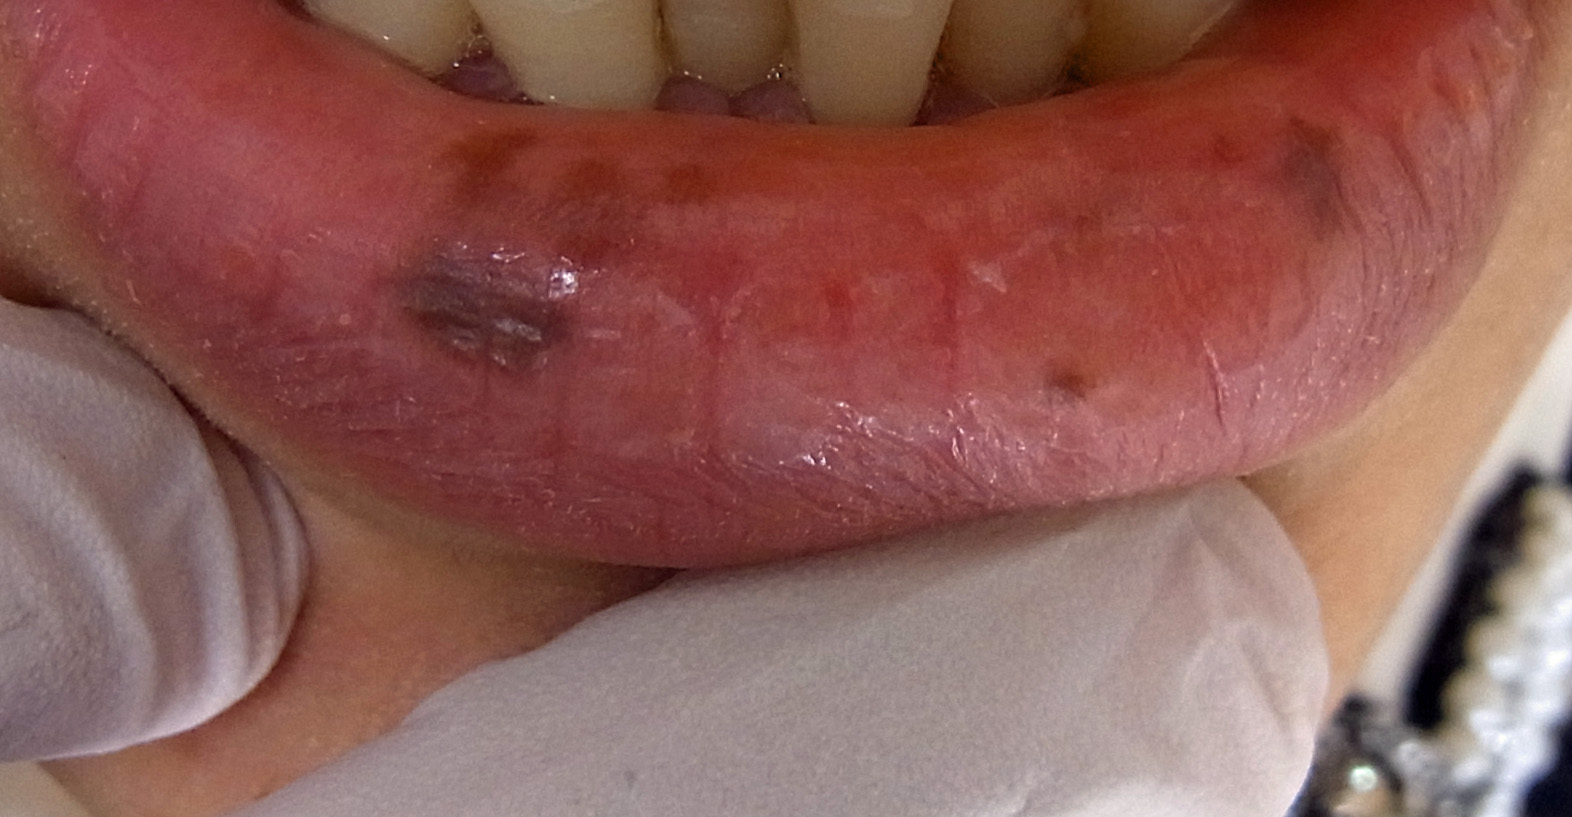

口唇の色素沈着です。大多数が下口唇に生じます。正式な日本語名はなく、口唇のシミのことです。症状は下口唇に多いことから、刺激因子として紫外線が考えられています。また、歯で口唇を噛む習癖が原因とも考えられますが、はっきりとした発生機序は不明です。単発のことが多いですが、多発することも少なくありません。20歳代、30歳代に多く、男女比は1:4で女性に多く見られます。自然に消えることはほとんどありません。口唇のホクロとは異なります。

唇のシミ治療の注意点

炭酸ガスレーザーでの治療はおこなってはいけません。瘢痕になります。

ピコ秒レーザーやQスイッチレーザーが最適な治療です。